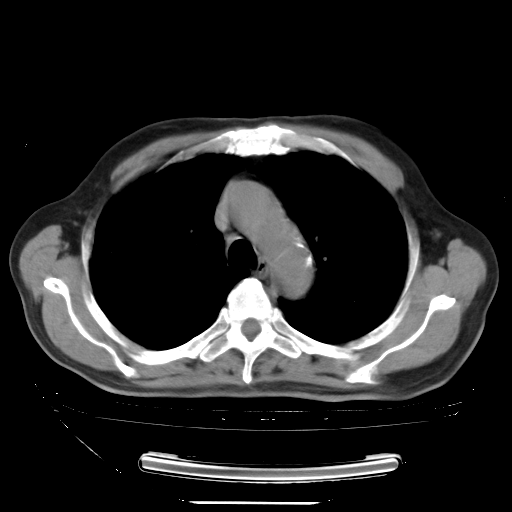

今天复查肺部CT,发现双肺广泛磨玻璃样改变。所以我把3月19日和5月9日相隔50天的肺部CT上传。请大家会诊。

2009年3月19日肺部CT片。

2009年3月19日肺部CT

5月9日肺部CT(在4月27日齐鲁医院肺部CT描述部分肺组织磨玻璃样改变,12天后肺组织广泛磨玻璃样改变)

2009年5月9日肺部CT

大致读了系列胸部CT:纵隔窗无明显异常,肺窗:从4、27至今:主要是双肺中下野外带可见毛玻璃样改变,目前处于急性肺泡炎阶段,至于原因考虑1、结替组织或胶原血管性疾病所致?2、恶性疾病如恶组在肺部所致的表现或细支气管肺泡癌?3、药物或其它原因如肺蛋白沉着症所致肺泡炎目前不太可能?总之,明天就去请我院的呼吸科、感染科、血液科和临免专家会诊哈。